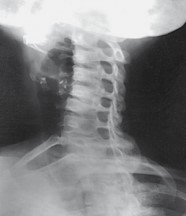

What does this image have?

shape distortion (elongated cervical spine), it is an oblique image